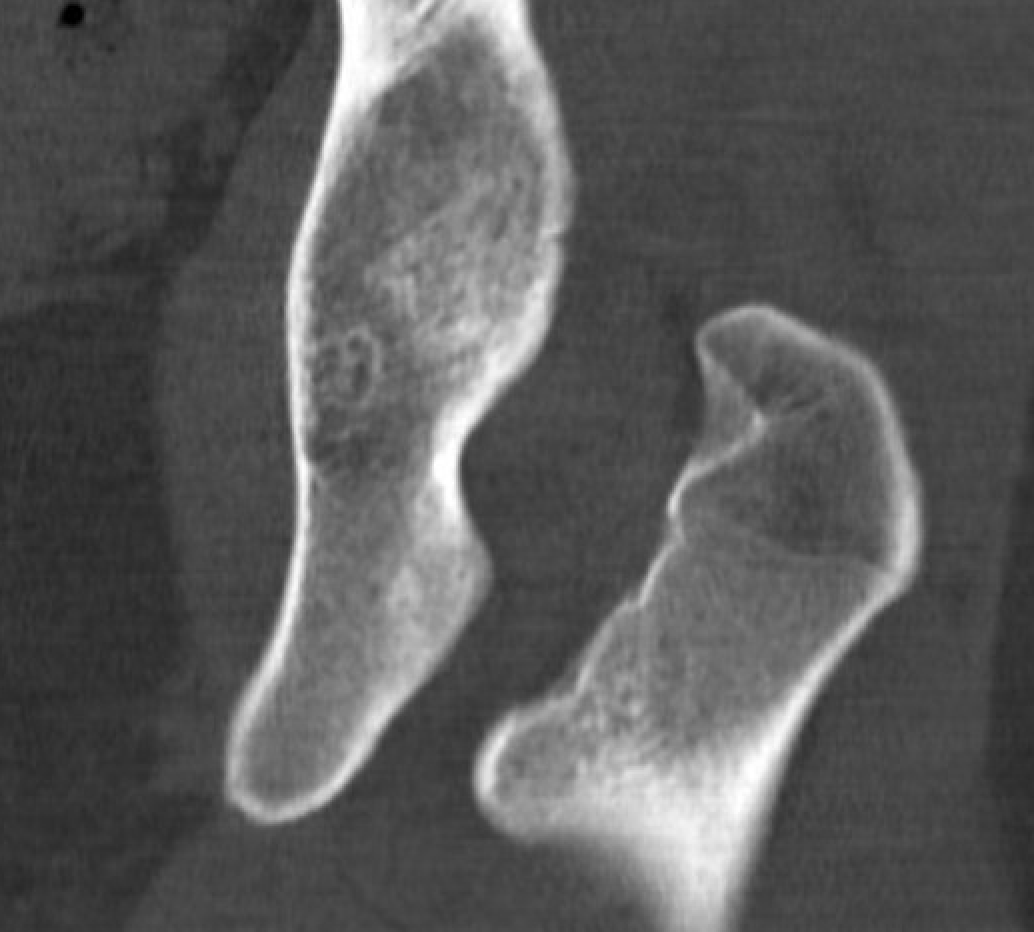

Reduced ischiofemoral space - distance between the lesser trochanter and the ischial tuberosity

Reduced quadratus femoris space - distance between hamstring tendon and iliopsoas

Inflammation / edema in quadratus femoris +/- fatty degeneration

CT